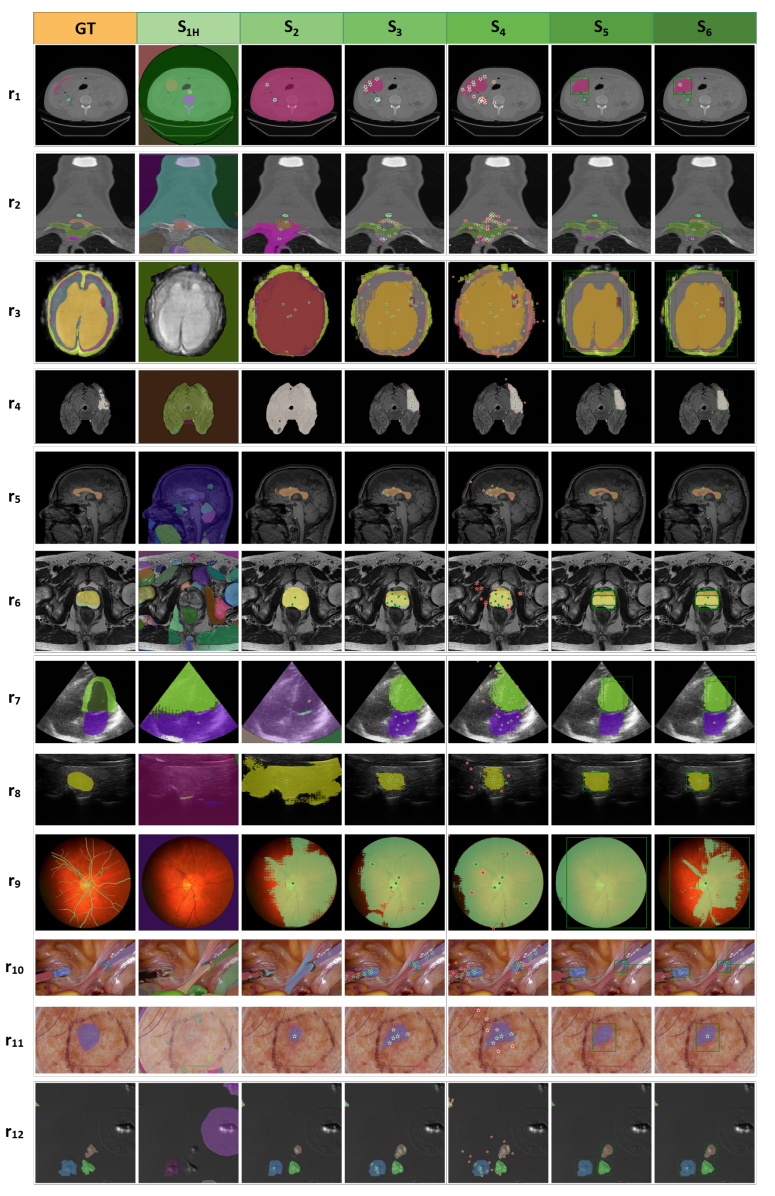

- 在Prompt模式下,加入更多前景点可显著提高SAM的分割结果。但医学影像中的前景和背景很容易混淆,随机加入负样本点可能会引起分割性能下降。此外,方框提示(S5)包含丰富的物体位置信息。因此,在我们的研究中,方框提示在大多数医学分割任务中比点提示表现好。在目前的研究中,混合策略(同时加入点提示和方框提示)的性能没有明显提升。这可能与SAM对混合提示的编码能力有关。图7和图8展示了SAM在各种测试策略下的可视化结果。

图8 典型的SAM失败案例